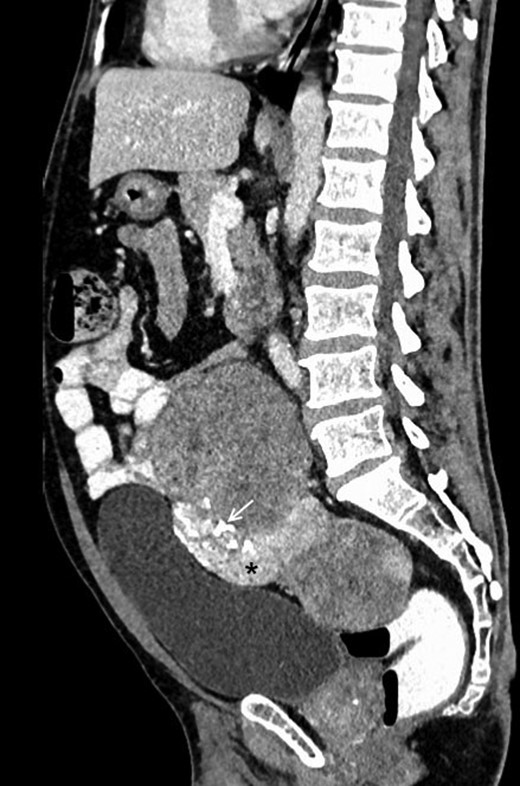

Contrast-enhanced sagittal reformatted CT section of the abdomen depicts a large enhancing mass posterior to the urinary bladder and anterior to the lower lumbar vertebrae and sacrum. The lesion is heterogeneously enhancing with a small hyperenhancing component (asterisk). Foci of calcification are noted within the lesion (white arrow). Note that the fat planes with the bowel and the urinary bladder are maintained.